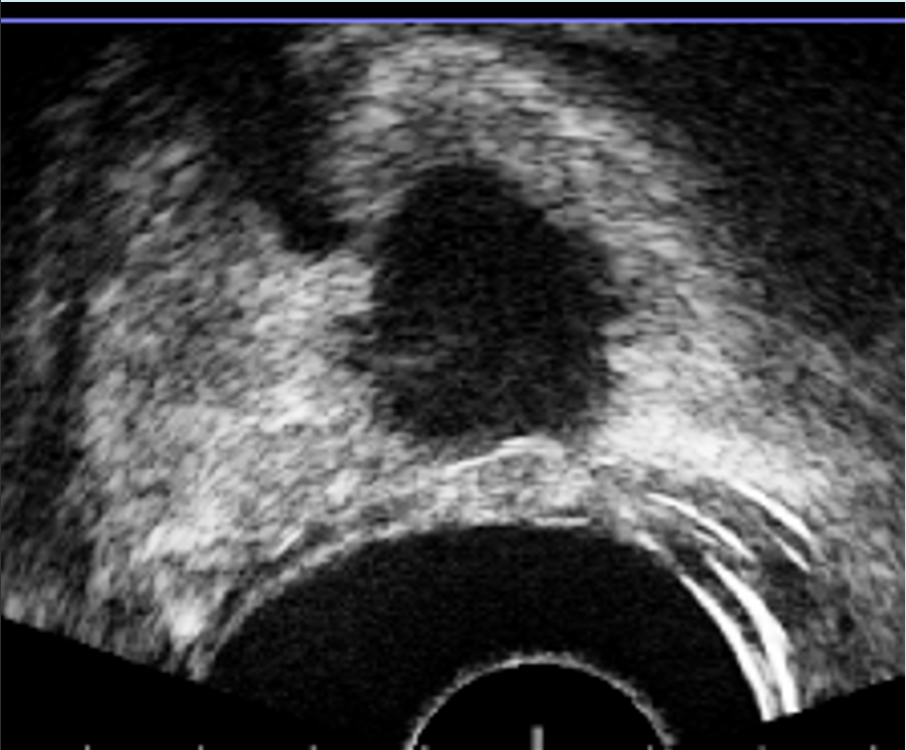

TRUS ofrece la capacidad de obtener imágenes en tiempo real, pero está limitada por una resolución espacial deficiente y una baja sensibilidad para el cáncer de próstata, ya que las lesiones a menudo pueden parecer isoecoicas en las imágenes de TRUS, lo que hace que sea difícil distinguirlas del fondo (1). Por el contrario, las imágenes de RM presentan lesiones prostáticas con detalles precisos y tienen una alta sensibilidad, pero no ofrecen la capacidad de adquisición de imágenes en tiempo real y orientación para la biopsia de manera oportuna o rentable. Los desarrolladores han creado estratégicamente plataformas de «fusión» para combinar imágenes de MRI y TRUS, lo que permite al urólogo acceso a la información esencial que ofrecen ambas modalidades (2). Una biopsia de fusión dirigida permite el muestreo de regiones específicas dentro de la próstata con lesiones identificadas en MRI, proporcionando así la posibilidad futura de eludir la necesidad de biopsias aleatorias «ciegas» en toda la glándula. (Figura 1).

Fig. 1. Biopsia por fusión. Correlación entre zona hipoecoica marcada en base derecha (flecha) con zona sospechosa marcada en resonancia (estrella).